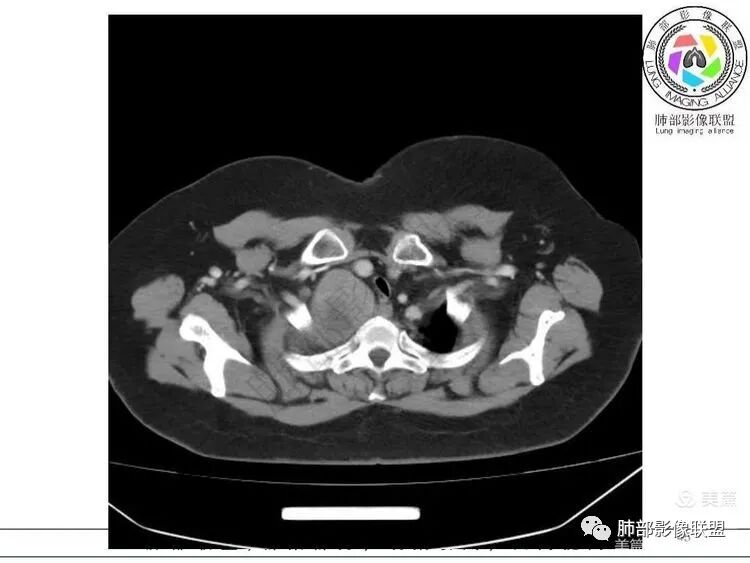

1. 右上胸廓入口区类椭圆形块影,边界清楚光整,纵向“嵌顿”于颈根部及上纵隔,向上推移右锁骨下动静脉,向外下方推移上肺胸膜及肺组织(肺血管、支气管),向前推移上腔静脉,界限清楚。

2. 块影不均匀轻度强化,可见较均匀实性区及液性密度区,未见积气、囊壁样结构、钙化或脂肪密度。可疑部分肋间动脉分支进入。

推压血管,进入颈部

南边:支持:神经源性,从病灶的形态突入颈部,跨多区域